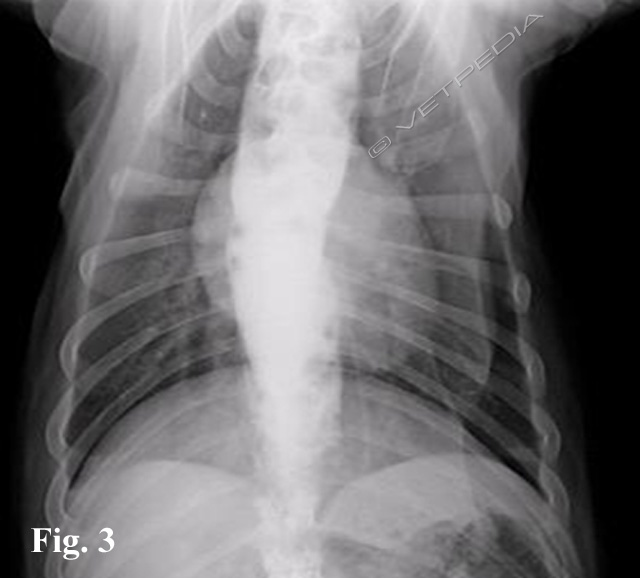

L’esame radiografico di norma si può eseguire senza sedazione; si può eventualmente eseguire una breve anestesia gassosa con induzione diretta. Viste le dimensioni della cavia, conviene eseguire di routine le proiezioni laterale e ventrodorsale di tutto il corpo, a meno che l’animale non sia gravemente debilitato e manovre stressanti poss...